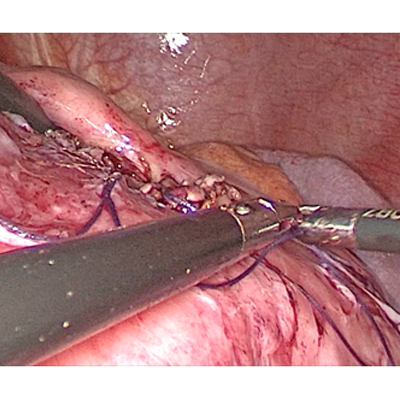

LAPAROSCOPIC SURGERY FOR PANCREATIC TUMOUR

LAPAROSCOPIC WHIPPLES PROCEDURE